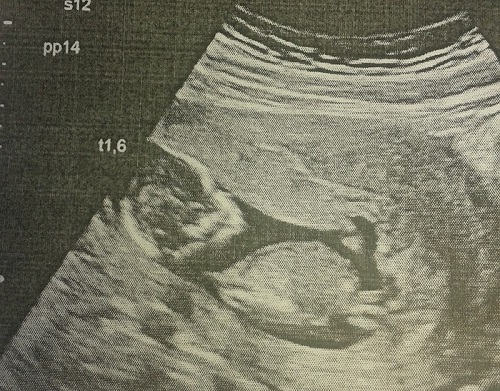

А это моя лялечка на 1м УЗИ 12 и 4))

21 июля на сроке 19 и 4 мы сделали второе скрининговое УЗИ, на котором нам сказали, что у нас будет ДОЧЕНЬКА!!! Я расплакалась сразу же и не могла успокоиться)))))) Врач спросила, что меня пол не устраивает, а я рыдая говорю - наоборот!!! Малышка развивается отлично, опережая срок на недельку. Из плохого только амниотический тяж, который еще в 12 неделек видели, но сказали, что он не контактирует с плодом и это не страшно, растянется со временем. Плацента поднялась, на 1м УЗИ была в области внутреннего зева. Весим мы 360 г))). В общем из рисков у нас только возраст - 37 лет. Кровь на второй скрининг не сдавала, и не буду, потому как первый скрининг показал очень низкие риски и генетик сказала, что если 2е УЗИ все будет хорошо, то кровь можно не сдавать.